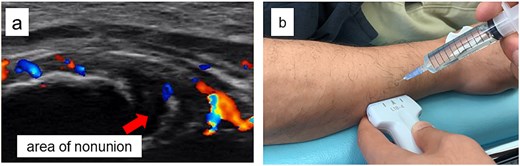

Ultrasound findings and images during the procedure. (a) Ultrasound image at the start of treatment showing marked Doppler signals around the nonunion site. (b) Dextrose injection into the nonunion site under ultrasound guidance.